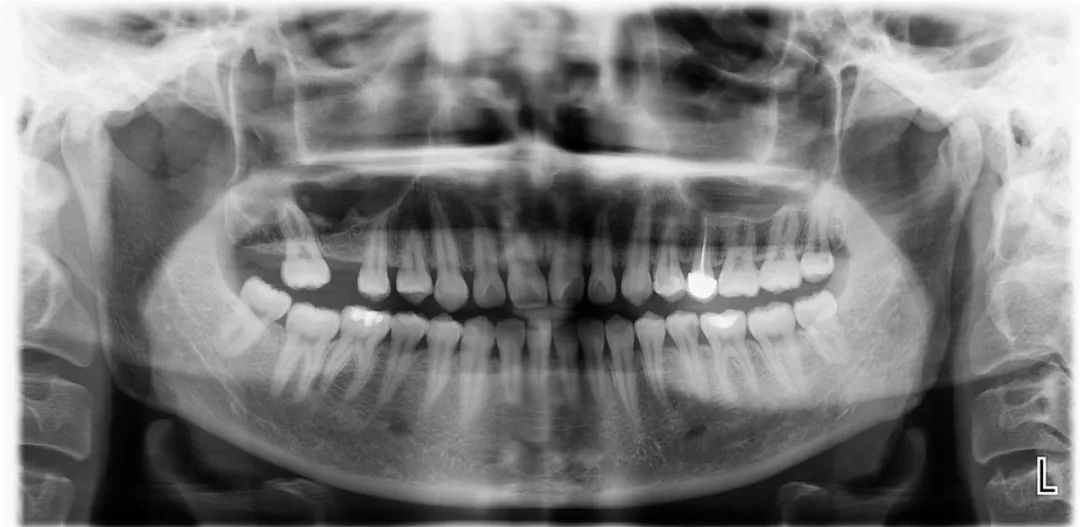

术后

学习班同时举办了Nobel、WEGO口腔种植实操培训和超声骨刀的操作培训。实操期间进行了5台种植手术,包括应用超声骨刀进行的高难度上颌窦外提升并同期植入种植体的手术。16名实操学员通过学习,掌握了种植的外科操作和种植体上部结构及印模技术,具备了开展种植牙技术的能力,所有学员满载而归。